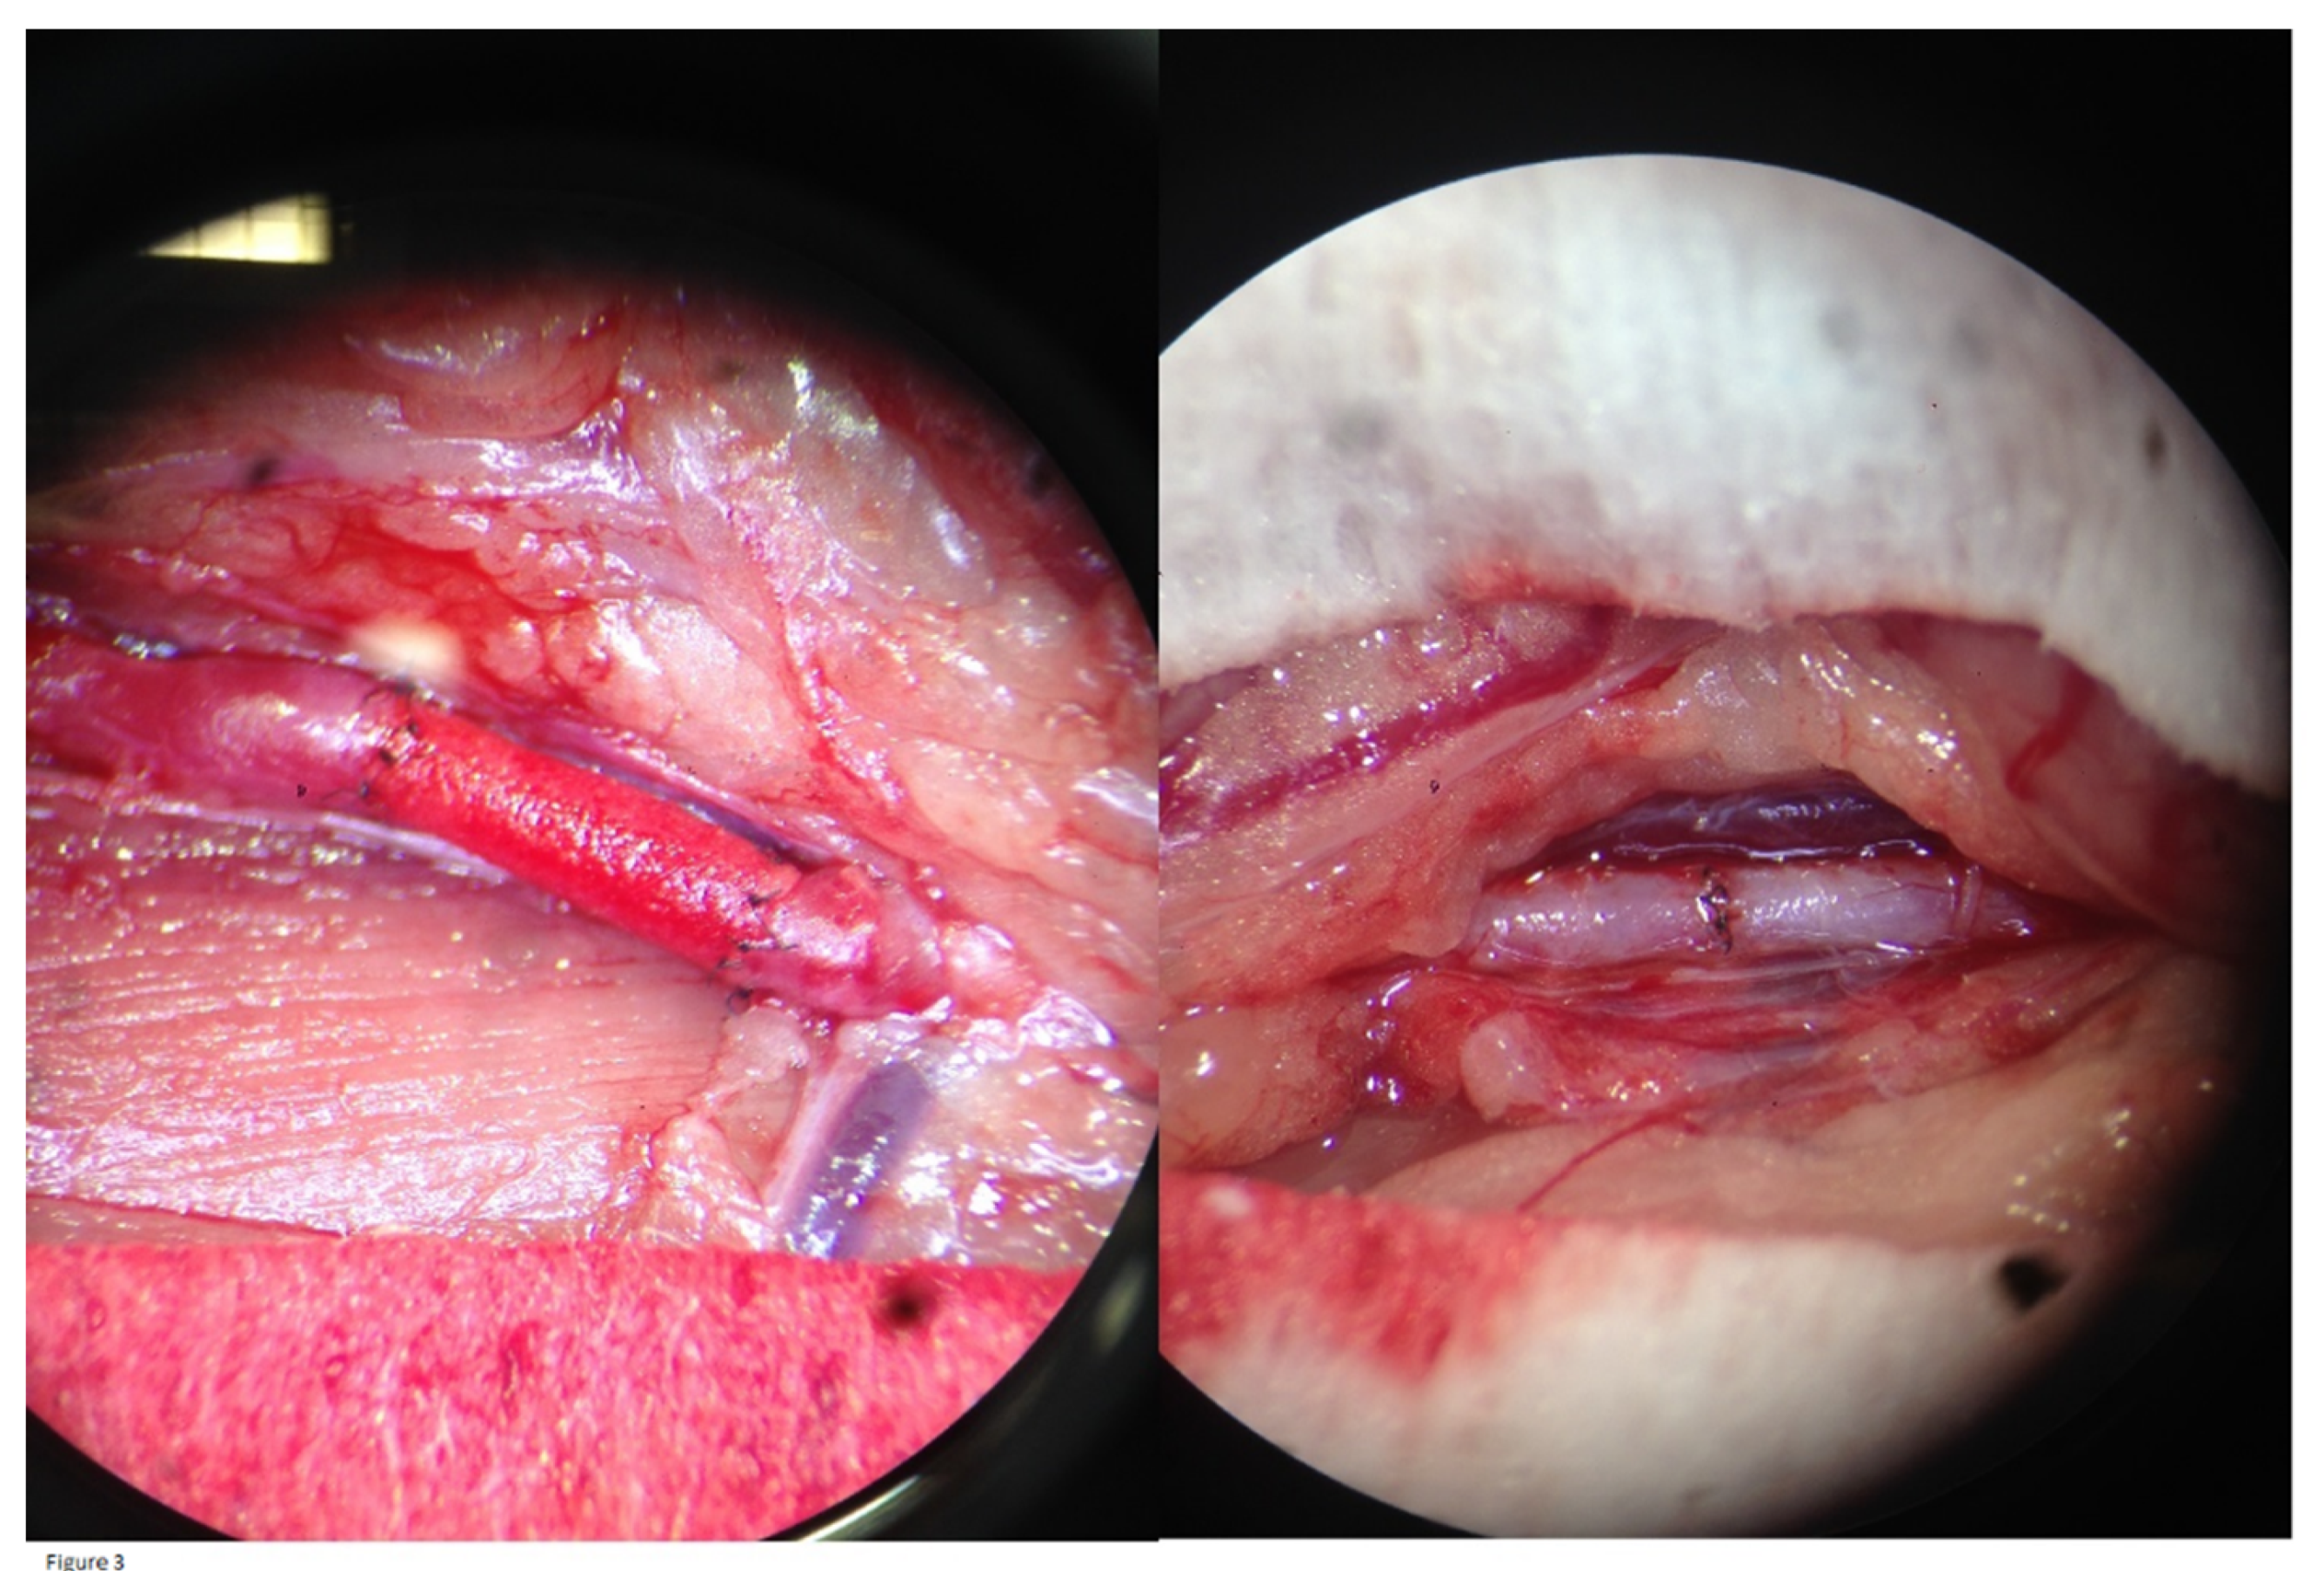

All rats were preoperatively healthy, as evaluated using standardized welfare control sheets. Throughout the experiments, a total of four rats from the intervention group were excluded from the study. In two of them, surgery was prematurely terminated without interposition of a graft, due to [1] technical problems with the microscope and [2] inability to reach sufficient levels of anesthesia. The other two rats died because of [3] major intraoperative bleeding due to accidental injury of the vena cava and [4] anesthetic intolerance. These four subjects were replaced by four unused Wistar Han IGS rats from the same lot. In the intervention and control group, all graft/control aorta anastomoses were tension-free and no major complications occurred. When releasing the vessel clamps after the procedure, an optical check of all graft/control aortas showed good expansile pulsations. The grafts became red and saturated with blood, indicating permeability to erythrocytes, but without any leakage at the anastomoses (Figure 3). The immediate postoperative outcome for all rats was clinically favorable.

H&E histological analyses after the 4-month-study period did not demonstrate any significant NIH in the ePU grafts (35 ± 42 µm, 54 ± 29 % of the graft length) and in 1/8 grafts, no NIH was apparent. NIH is a consequence of shear stress caused by turbulent blood flow and, as mentioned previously, normally only reaches its maximum after one month. 36 Thus, because there was only minimal NIH after a 4-month-period, it was unlikely that there would be any further increases over a longer period of time. Interestingly, in a recent report from Bergmeister et al. it was demonstrated that there were only 2/20 ePU grafts with visible NIH after 3 months (mid graft: mean 198 ± 73 μm, anastomoses: mean 159 ± 71 μm). There are two potential reasons for the smaller NIH rates that were found in the Bergmeister et al. study compared to our study: [1] size-mismatch; the ID of the infrarenal aorta of the rat ranged from 1 to 2 mm. 19 Size-mismatch in our study may have led to shear stress conditions and subsequent NIH. However, as is evident from Figure 3, there was no size mismatch in our study. 37 [2] NIH was caused by incomplete endothelialization, which is more likely, as described below. 34

Figure 3. Implantation surgery. Left: intervention group, end-to-end anastomosis of a 1.25 mm ID ePU graft to the infrarenal aorta. Right: control group, end-to-end anastomosis of partially transected infrarenal aorta.